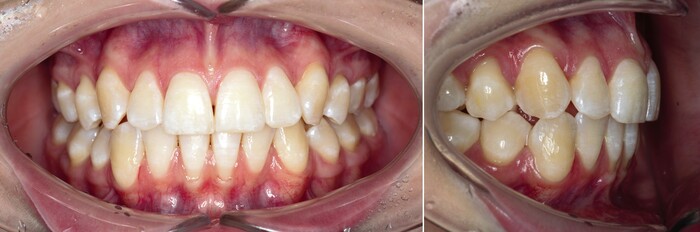

Я согласен, что эстетика хромает. Давно пора менять временную коронку на постоянную, что улучшит результат. Но, как я говорил, все упирается в финансы.

С другой стороны… с этого мы начали:

а на этом остановились:

Пациентке настоятельно рекомендована консультация ортодонта. Но я не уверен, что она до нее дойдет. Но если это случится, я обязательно буду дополнять статью фотографиями и комментариями к ним.